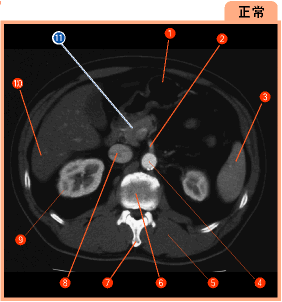

▲188ページ 正常画像内(2007/2/5)

※11の引き出し線の位置が誤っておりました(下は正しい画像です.青線で示しています)

| ● |

|